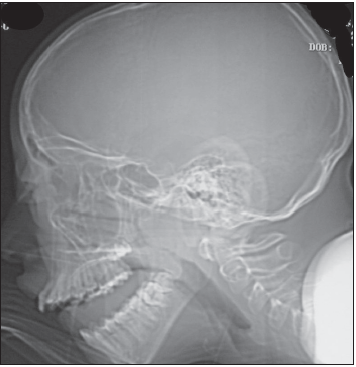

Intraorbital abscess: The radiographs demonstrate opacity of the ethmoid air cells on the left (A and B, blackarrows) with increased opacity of the left maxillary antrum, which is best seen on the frontal view (A, red arrow). The sphenoid and frontal sinuses are unremarkable. The increased density seen on the films results from the filling of the normally aerated sinuses with opaque material (in this case, mucus).

Close inspection also reveals increased density of the left orbit (A, yellow arrow). This density is attributable to edema.